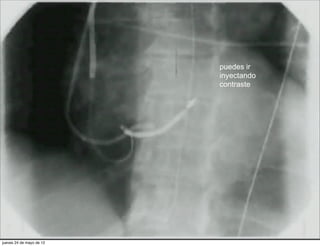

puedes ir

inyectando

contraste

puedes ir inyectando contraste jueves 24 de mayo de 12